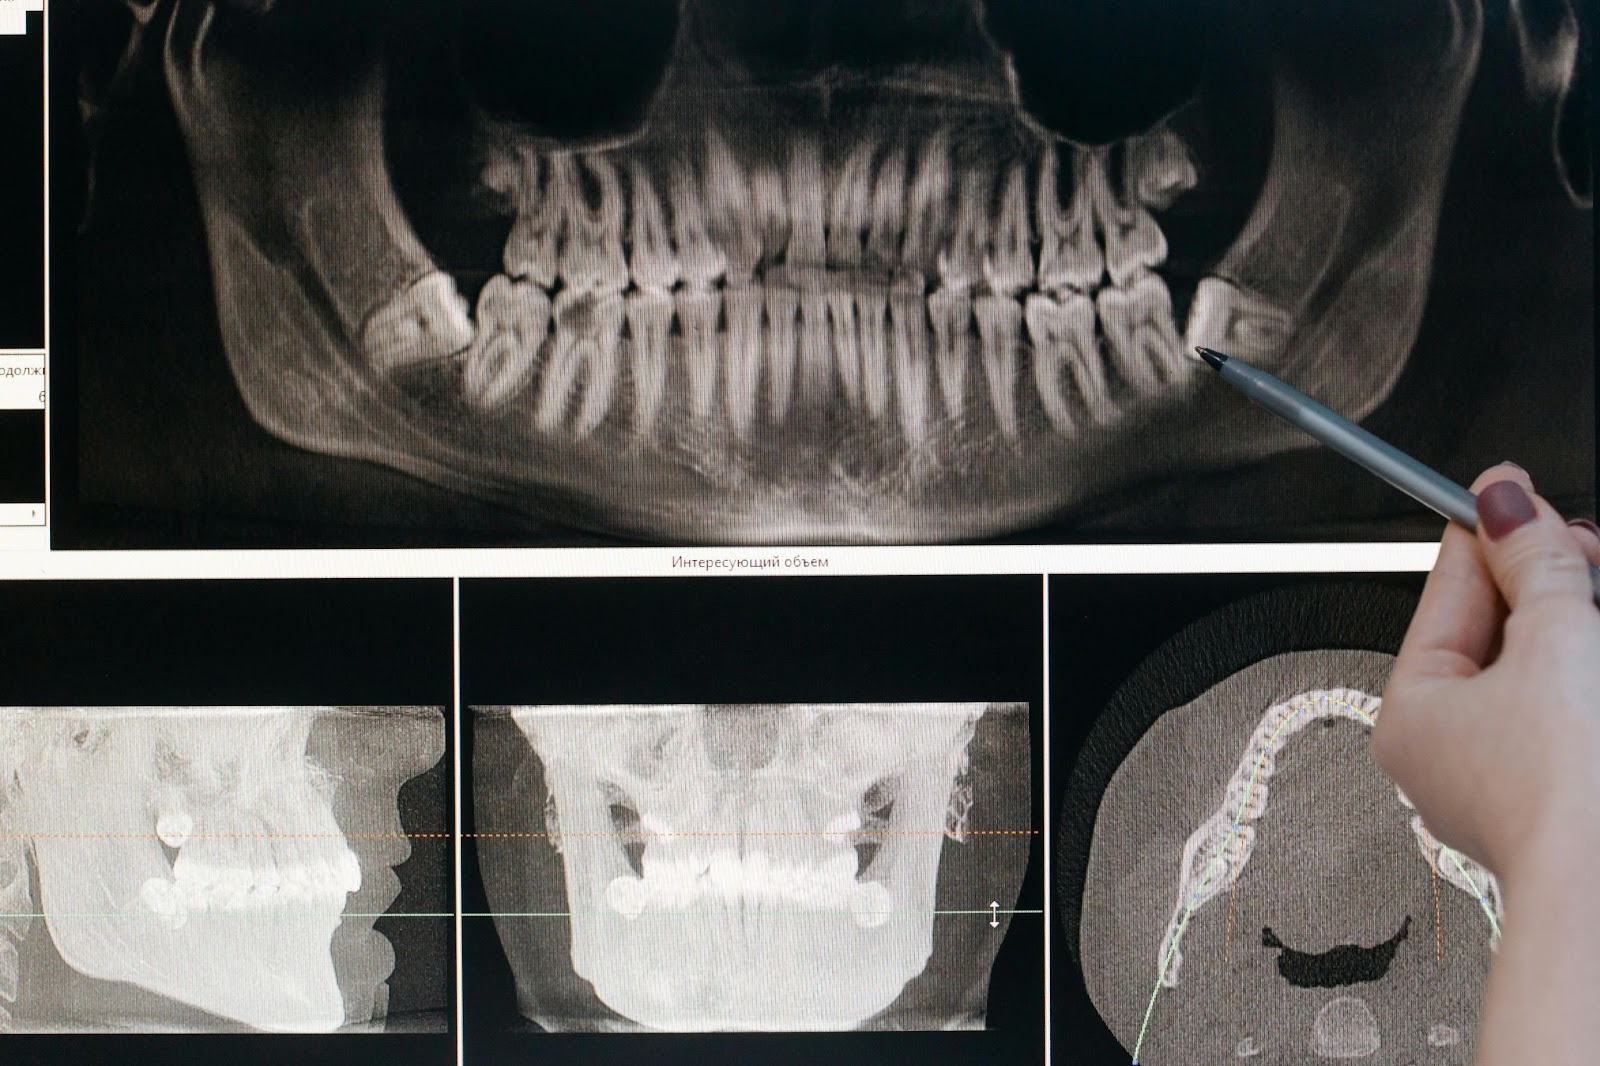

- Konsultasi dan Evaluasi: Dokter gigi akan memeriksa kondisi gigi gingsul dan area sekitarnya, serta melakukan rontgen untuk menilai posisi dan kondisi gigi tersebut.